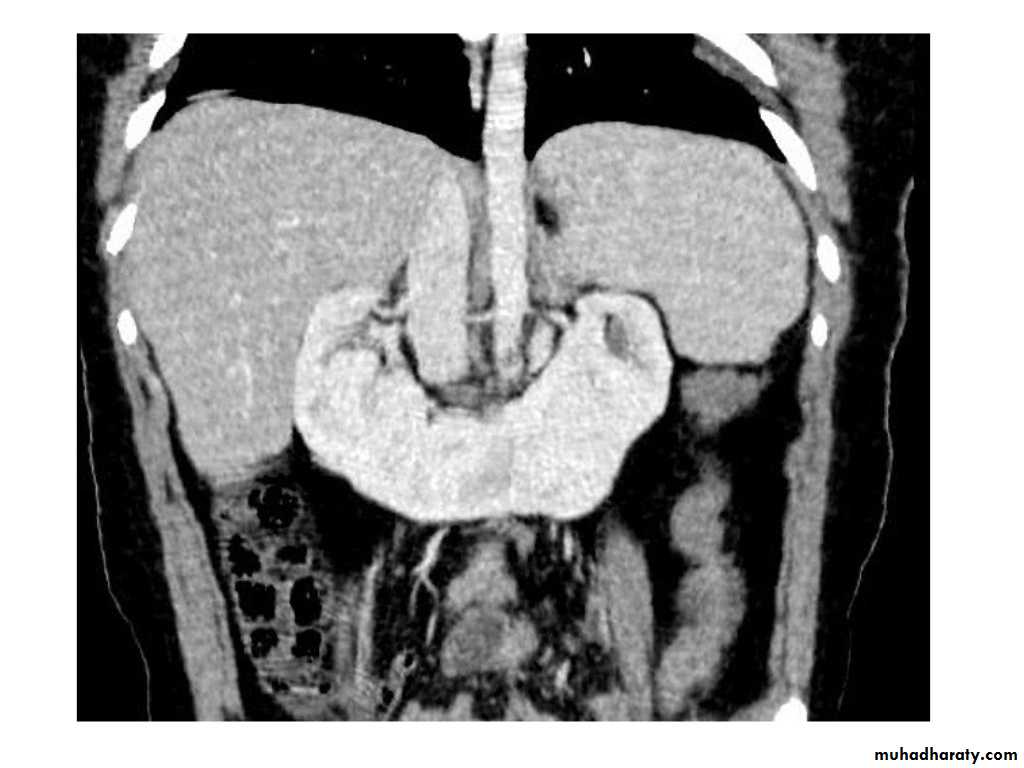

IVU shows

1. The kidneys at low position .2.Close to the spine with long axis parallel to the spine

3. Malrotation manifested by medially directed calyces.

4- The renal pelvis and ureters are anterior and lateral in position.

5- Hydronephrosis and calculi highly associated.